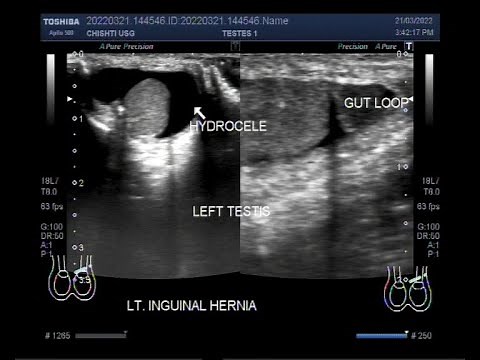

Inguinal Hernia - Hernia Inguinal

Inguinal Hernia CT - Hernia Inguinal